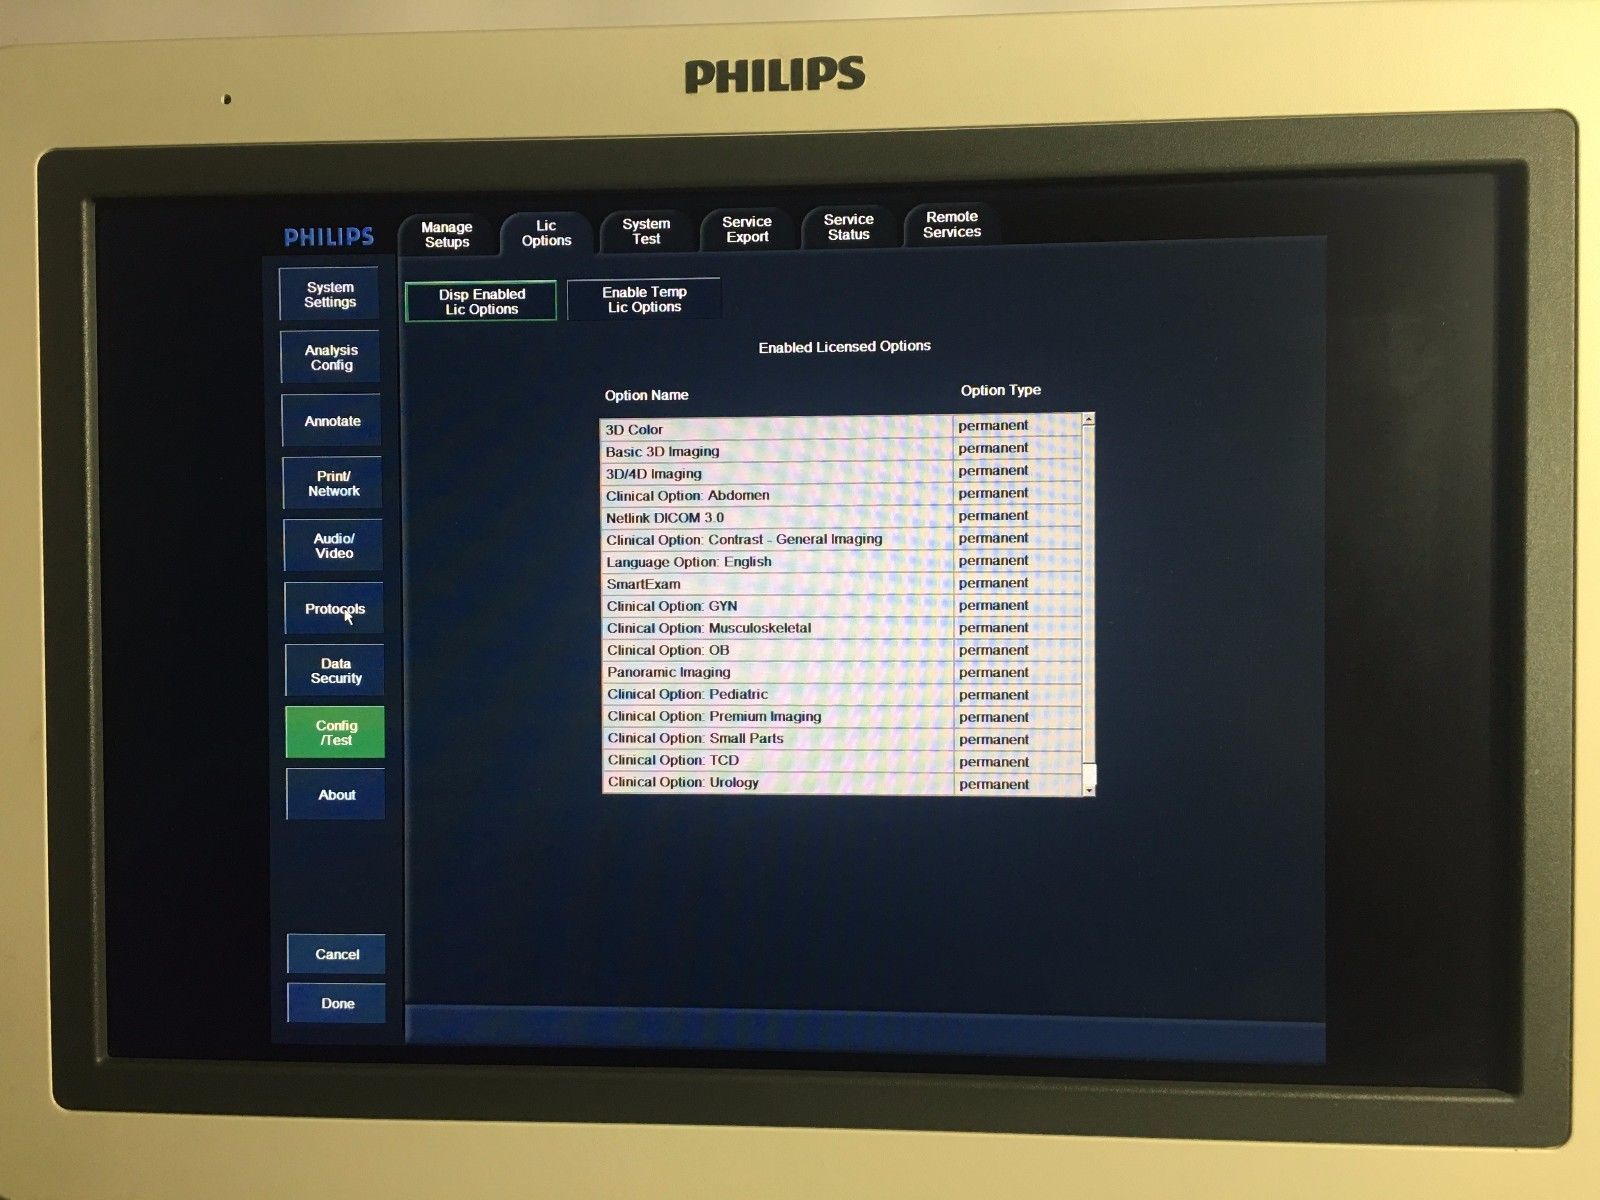

Acquire a trusted healthcare companion with our Philips IU22 3D/4D Ultrasound System, now available for purchase. This pre-owned model, possessing a legacy of reliability, is being offered in an excellent operational condition and comes with a complete set of four probes.

Comprehensive Functionality: Despite showing minimal signs of cosmetic wear, the unit remains fully functional and geared for immediate clinical deployment. All probes have been diligently tested to ensure optimal performance. Extensive care has been taken to maintain the system, reaffirming its condition akin to new.

Philips Quality Assurance: As a testament to its prowess, the IU22 model comes with Philips's renowned brand assurance, guaranteeing you a quality product that adheres to the highest industry standards.

The MPN 8500-0064 model awaits your practice, aptly supporting a diverse range of diagnostic requirements. Though UPC information is not specified, the significance of its capabilities stands undisputed within the medical community.